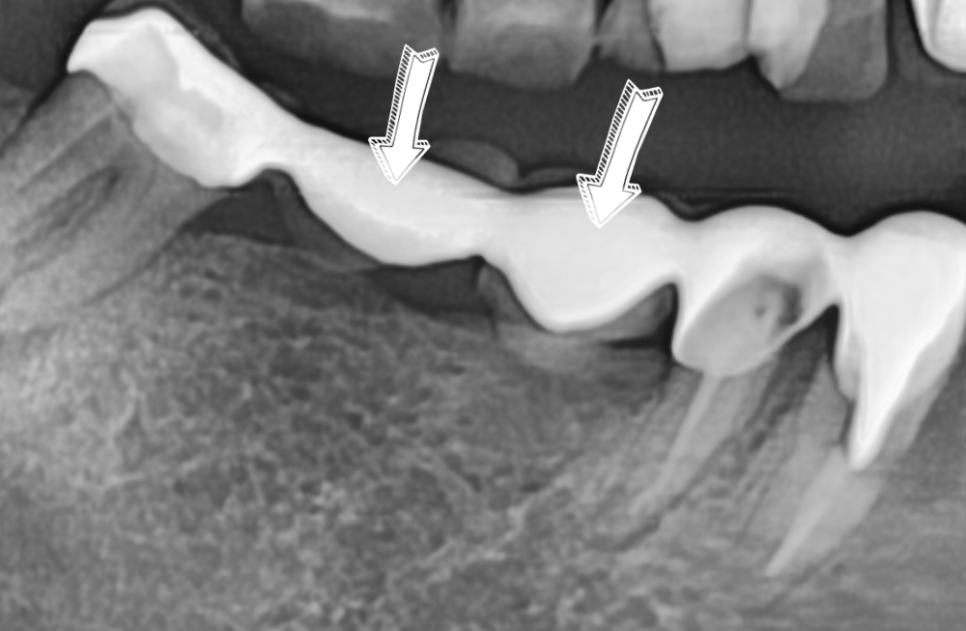

과도한 하중으로 부러진 보철물

이번 환자분의 경우에도 CT를 분석해 보니

다행히 뼈의 폭이 5mm~7mm 정도로

충분히 두꺼웠습니다.